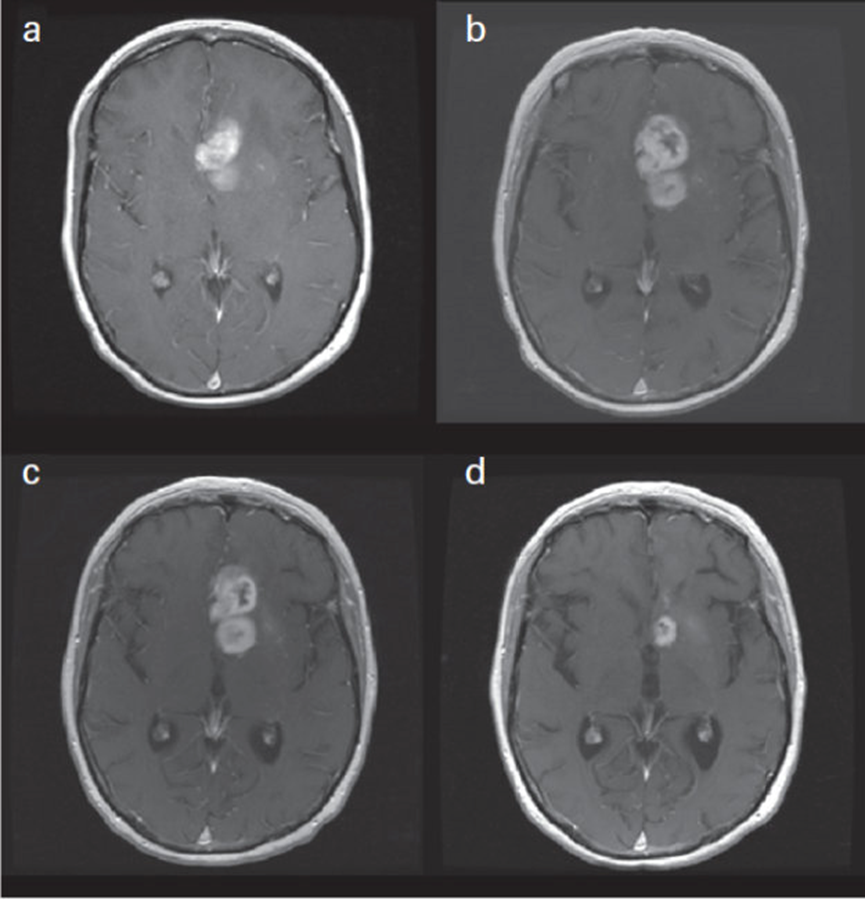

圖A顯示的是病理證實為膠質(zhì)母細胞瘤后兩天的掃描結(jié)果。圖B顯示的是放療后的掃描,結(jié)果顯示異常增強區(qū)域的擴大,類似于疾病進展,提示可能存在假性進展(PsP)。圖C顯示的是四周后的隨訪MRI,病灶無明顯變化,且治療方案未改變。圖D顯示的是完成8個周期的替莫唑胺治療后的掃描,顯示腫瘤(或原本被認為是腫瘤)有所改善,增強區(qū)域顯著改善,且治療方案未改變。因此,這是一個假性進展非常典型的例子。

更新的高等級膠質(zhì)瘤反應(yīng)評估標(biāo)準:神經(jīng)腫瘤學(xué)工作組的反應(yīng)評估。J Clin Oncol. 2010年4月10日;28(11):1963-72,第1965頁。